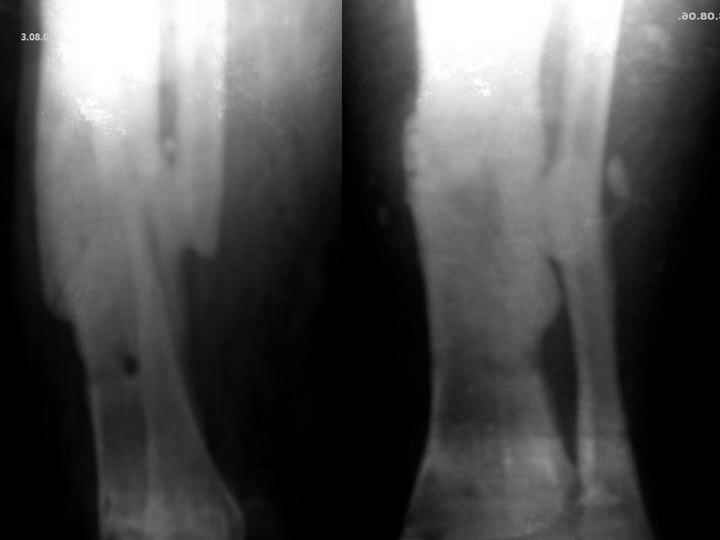

Мужчина, 29 лет. Состоит на лечении в ЦРБ.Диагноз: Замедленно сростающийся со смещением повторный перелом обеих костей левой голени вс/3-н/3, состояние после ВЧКО, хронический остеомиелит костей левой голени, свищевая форма,трофический синдром, смешанная контрактура левого коленного, голеностопного суставов.

Травма 20.12.04. - открытый 2Б тип, оскольчатый перелом обеих костей левой голени в с/3-н/3 сосмещением отломков (ДТП). 20.12.04.- ВЧКО костей голени АВФ спице-стержневого типа, ПХО ран.Лечился амбулаторно. Перелом длительно не сростался. АВФ демонтирован 22.06.05., разрешена нагрузка на ногу, после чего появилась подвижность в области перелома. 8.07.05. - ВЧКО, туннелизация по Беку. Течение осложнилось развитием спицевого остеомиелита, 1.11.05. АВФ демонтирован, получал консервативное лечение. После нормализации состояния 17.11.05.- секвестрэктомия, ВЧКО голени.12.04.06. АВФ демонтирован.

3.06.06.повторная травма - закрытый повторный перелом левой б/б кости в с/-н/3, лечился методомгипсовой иммобилизации.

Место болезни - ось голени искривлена. Kеллоидные рубцы в местах проведения спиц, по передней поверхности голени. По передней и внутренне-боковой поверхности голени в определяется 3 свища с умеренным серозным отделяемым. Отек голени и сустава, движения в коленном и голеностопном суставах ограничены, неврологических расстройств в стопе нет.

Снимки, конечно, оставляют желать. Ладно, пробуем предложить решение в условиях недостатка информации. В том числе не зная о доступных на месте методах лечения.

А фистулографию делать не пробовали? В смысле, это остеомиелит спицевых каналов, или инфицированное несращение?

Если первое - снова остеосинтез аппаратом, остеотомия малоберцовой кости, дозированное исправление оси и длины.

Если инфицированный ложный сустав - лучше перевести пациента в более оснащенное чреждение.